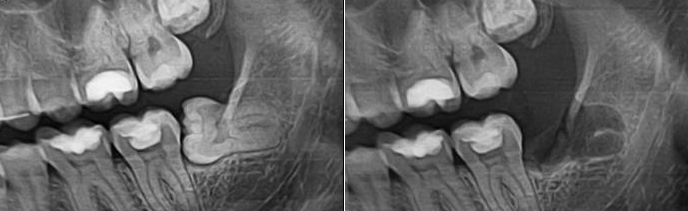

Удаление коренных зубов: фото до и после

Сложное удаление коренных зубов требуется если:

• зуб имеет искривленные корни;

• коронка разрушена ниже уровня десны;

• зуб не прорезался полностью или имеет горизонтальное положение.

Сложность удаления коренного зуба заключается в том, что врачу приходится разрезать десну, чтобы отслоить ее от кости. Затем бормашиной высверливается некоторый объем костной ткани — это позволяет получить доступ к зубу, подлежащему удалению. Иногда при сильно искривленных корнях бывает нужно распилить межкорневую перегородку и извлекать их по отдельности.